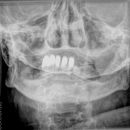

Densfraktur